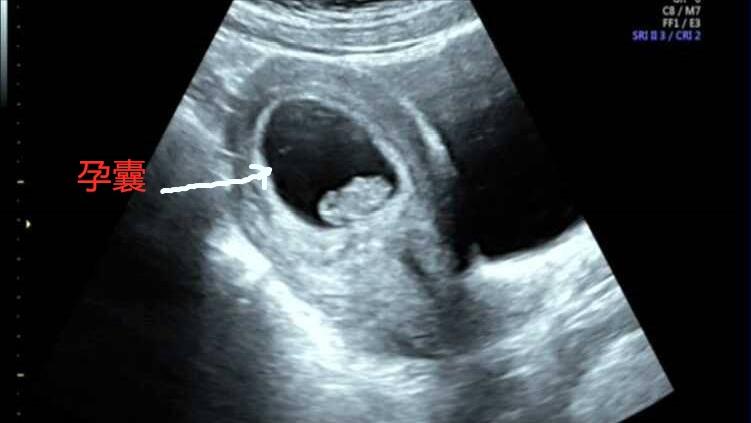

另外,还要明确孕囊着床的位置是否在子宫里面。在怀孕的女性中可能有部分人会存在宫外孕的情况。对于此类人群,是不能进行药流的。所以说,并不是所有的妊娠类型都适合进行“药流”。